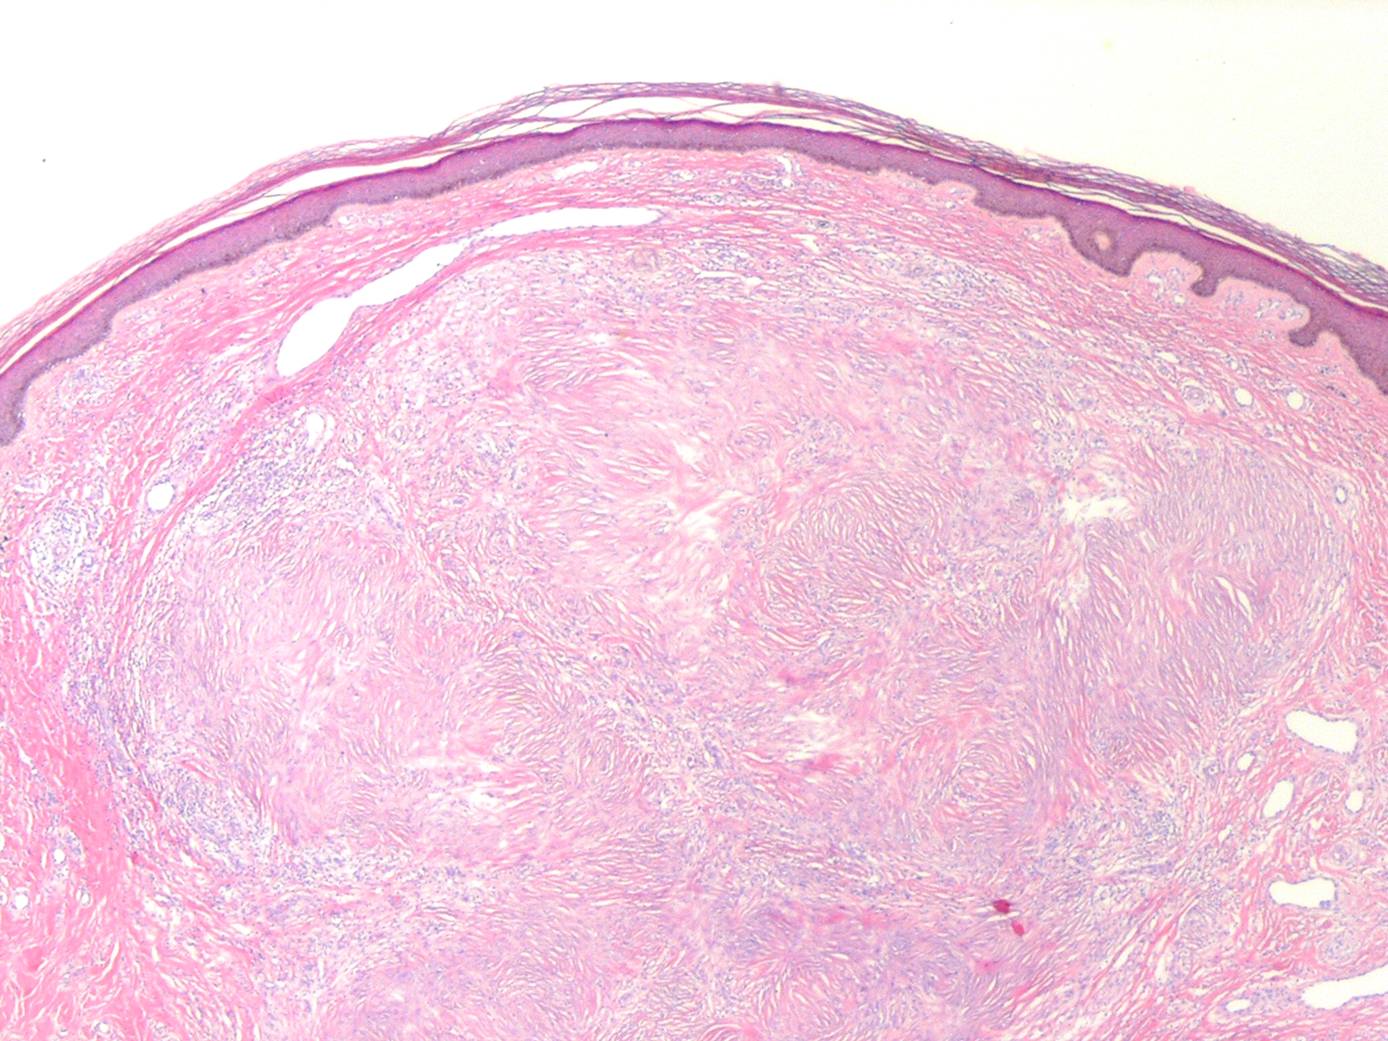

Sclerotic fibroma = الليفوم المتصلب